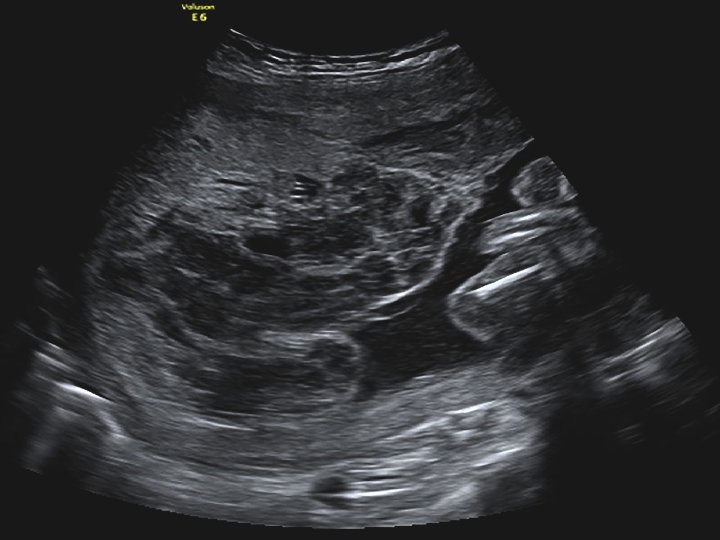

FETAL BÜYÜME BOZUKLUKLARINDA TARAMA VE TANI • Fetal büyüme bozukluklarının taranmasında medikal ve obstetrik öyküyü takiben fizik muayenede gebeliğin 24 - 38. haftaları arası uterus fundus yüksekliğinin ölçümü kullanılmaktadır. • Anormal fetal büyüme tipik olarak ultrasonografide fetusun güncel biyometrik ölçümleri ile gestasyonel yaş için beklenen biyometrik ölçümleri arasında tutarsızlık olması ile tanınır. • Tanı büyük ölçüde doğru gebelik haftasını belirlemeye bağlıdır!

• Anormal biyometri saptanan hastalarda anormal fetal büyümenin fetal, plasental veya maternal nedenlerinin belirlenmesi amacıyla klinik ve ultrasonografik muayene yapılması gerekir. • Tahmini fetal ağırlığın saptanması için birçok formül önerilmiştir. • Bu formüllerin birçok parametre içermesine (biparietal çap, oksipitofrontal çap, baş çevresi, femur uzunluğu, abdominal çap ve abdominal çevre) karşın tahmini fetal ağırlıkta yanılma ortalama %10 -15 arasındadır ve bu oran %25’e kadar çıkabilmektedir.